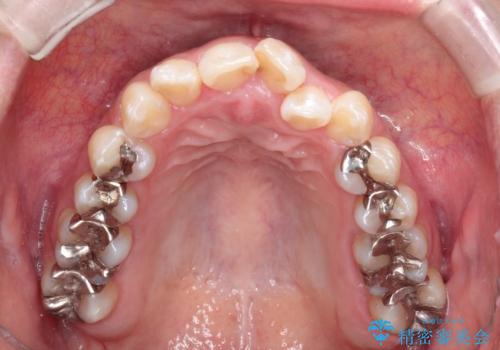

- 前歯のガタツキが気になると来院されました。

奥歯の噛み合わせは綺麗に噛んでいたため、前歯の叢生(でこぼこ)に集中して治療するように計画しました。

奥歯の噛み合わせは整っていたため、前歯の並びを美しく修正することに専念できました。

前歯のガタツキを改善する治療法として、マウスピース矯正が適していることが多いです。